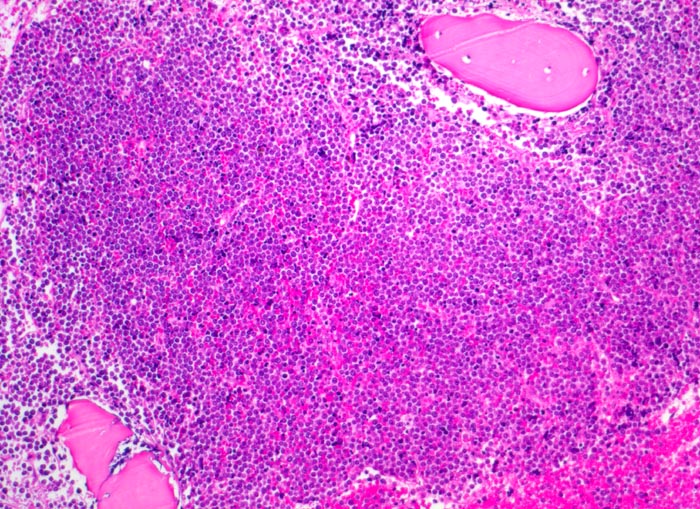

Akute lymphatische Leukämie (ALL)

Knochenmark, Beckenkamm

Verdrängung des Fettmarkes durch diffuse undifferenzierte Tumorzellrasen. Weitgehende Verdrängung der Myelo-, Erythro- und Megakaryopoese (monotones Bild).

Vergrösserte Lymphknoten, Hepato-Splenomegalie. Knochen- und Gelenkschmerzen, vermehrte Müdigkeit.

Histologie

100

13

männlich